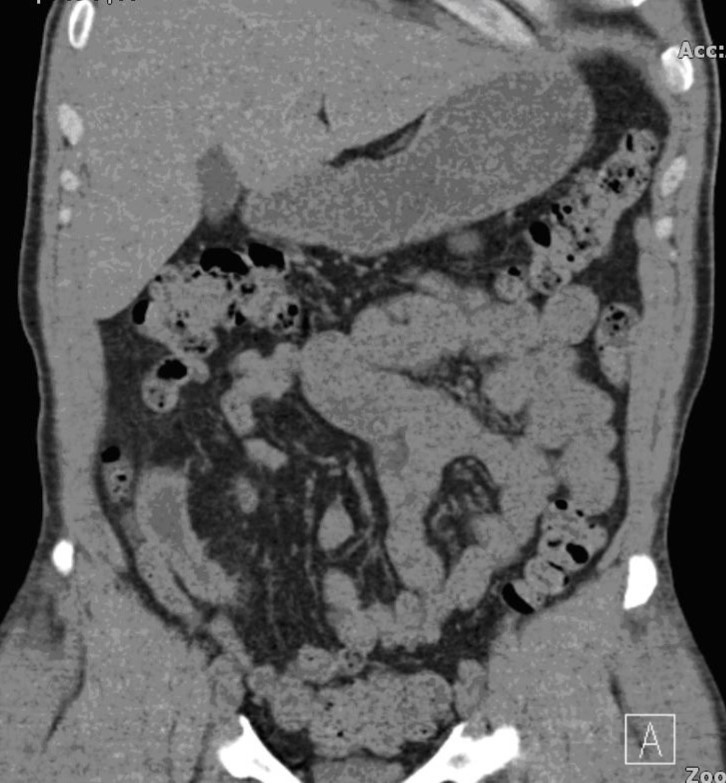

We report a case of a gentleman with spina bifida who underwent urinary diversion in the form of an ileal conduit as a child and presented 40 years later with worsening renal function that was picked up by his general practioner during routing investigations. Clinical examination revealed a hard mass superomedial to the right parararectal stoma. An initial ultrasound scan showed bilateral hydronephrosis and a possible calculus in the conduit. A subsequent CT KUB showed a 13 cm x 4 cm calculus occupying most of the conduit causing outflow obstruction (Figure 1). He also had a 2cm left renal calculus. Following a Foley catheter insertion into the stoma under image guidance, his renal function returned to normality. The patient was counselled for both the open and endoscopic approach.

Figure 4.Post-operative CT scan revealing a stone free ileal conduit.